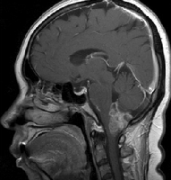

脑干肿瘤在成年患者中并不常见。出现的平均年龄是生命的四个十年,总生存期约为54-64个月。它们在流行病学数据中占全部脑肿瘤的小于2%。那些仅位于延...

延髓胶质瘤属于脑干胶质瘤的异质组。这些肿瘤起源于髓质,并可延伸至邻近结构,如脑桥、小脑下梗、小脑和脊髓上部。脑胶质瘤发生在儿童和成人患者...

延髓胶质瘤是绝症吗?脑干肿瘤在成人患者中很少见。出现的中位年龄为生命的四个十年,总生存期约为54-64个月。它们占流行病学数据中全部脑肿瘤的2...